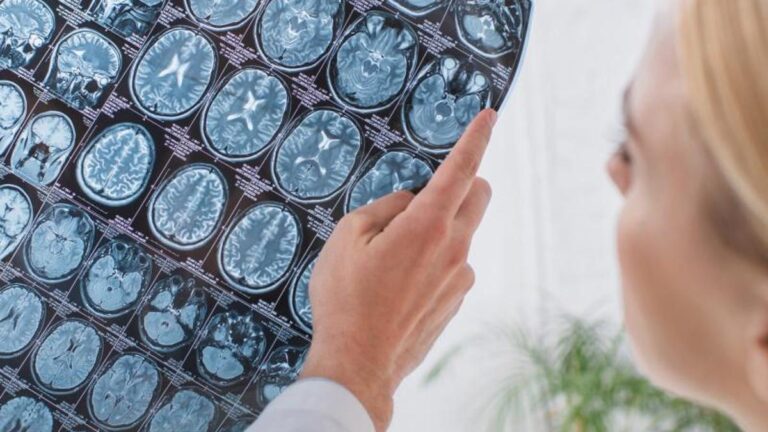

Beyin Sağlığı Uzmanından Yararlı Beslenme Önerileri